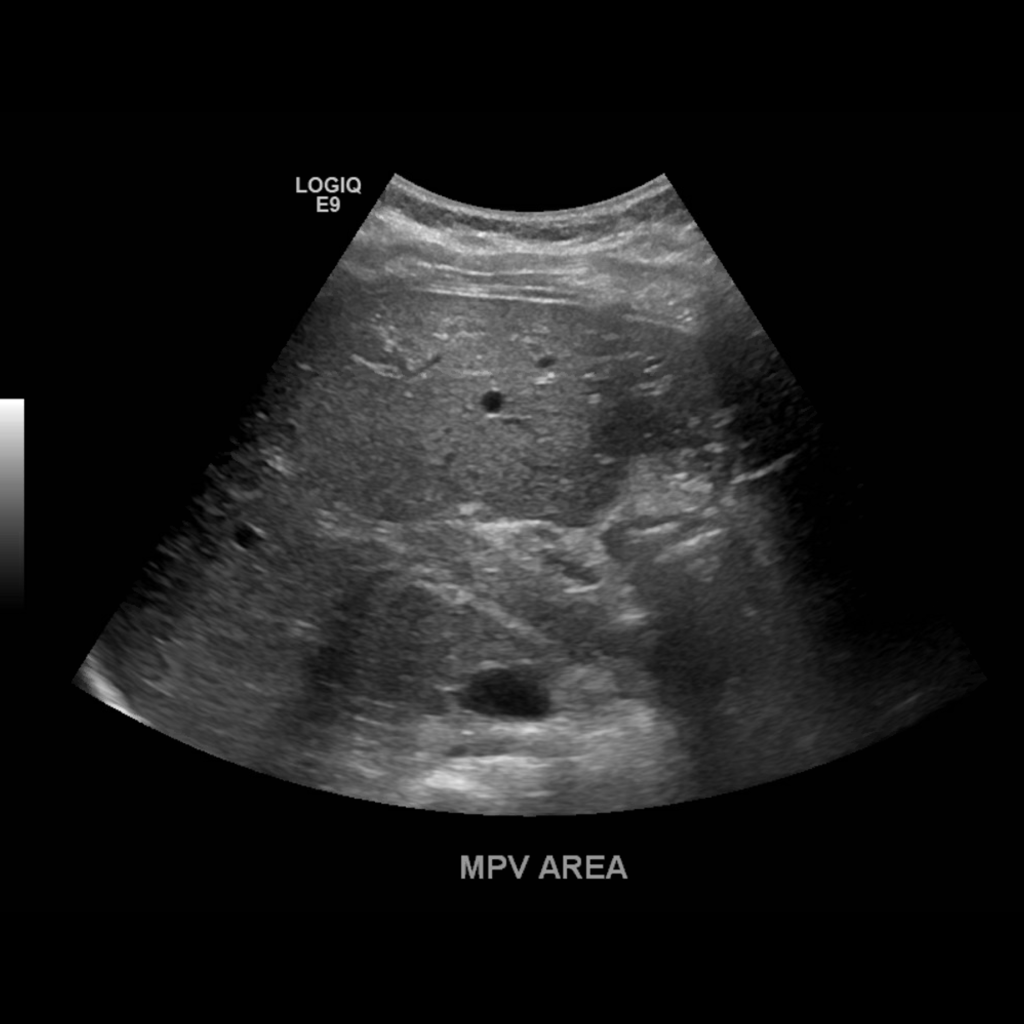

When the portal vein enters the liver it bifurcates into right and left main branches. The right portal vein bifurcates into an anterior and posterior branch which feed segments 5, 6, 7 and 8 respectively, whereas the left branch feeds segments 2, 3 and 4. The normal diameter of the main portal vein is 1.3 cm (some institutions use 15. as the upper limit) Normal flow is hepatopetal (towards the liver), with a flow velocity between 15-40 cm/s. Be sure to make sure you color is inverted and your approach is optimized. In the main portal vein below flow is hepatopetal in both images, the only difference is transducer angle, tilt and approach.

Portal Vein Bifurcation